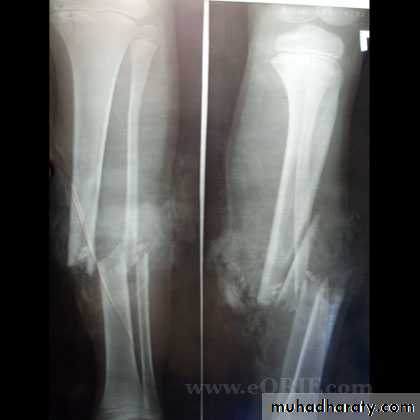

FRACTURES OF TIBIA AND FIBULA

Mechanism of injury1-Indirect injury is usually low energy; with a spiral or long oblique fracture one of the bone fragments may pierce the skin from within.

2-Direct injury crushes or splits the skin over the fracture; this is usually a high-energy injury and the most common cause is a motorcycle accident.

The limb should be carefully examined for signs of soft-tissue damage: bruising, severe swelling, crushing or tenting of the skin, an open wound, circulatory changes, weak or absent pulses, diminution or loss of sensation and inability to move the toes. Any deformity should be noted before splinting the limb. Always be on the alert for signs of an impending compartment syndrome.X-ray

The entire length of the tibia and fibula, as well as the knee and ankle joints, must be seen. The type of fracture, its level and the degree of angulation and displacement are recorded Spiral fractures without comminution are low energy injuries. Transverse, short oblique and comminuted fractures, especially if displaced or associated with a fibular fracture at a similar level, are high energy injuries.Management

1-Closed intramedullary nailing This is the method of choice for internal fixation. The fracture is reduced under x-ray control and image intensification. For diaphyseal fractures, union can be expected in over 95 per cent of cases. However, the method is less suitable for fractures near the bone ends.

2-Plate fixation is best for metaphyseal fractures that are unsuitable for nailing. It is also sometimes usedfor unstable tibial shaft fractures in children.

3-External fixation This is an alternative to closed nailing; it avoids exposure of the fracture site and allows further adjustments to be made if this should be needed.